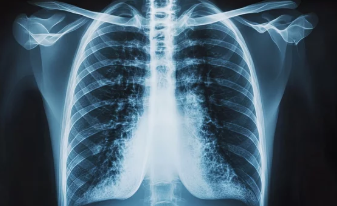

폐기흉(기흉, Pneumothorax)은 폐에 공기 주머니(기낭)가 터지거나 손상되면서 공기가 흉강(가슴막)으로 새어나와 폐가 수축하는 질환이다.

특히 젊고 마른 남성, 흡연자, 폐 질환이 있는 사람에게서 더 흔하게 발생할 수 있으며, 심한 경우 호흡 곤란 및 응급 상황이 발생할 수 있다.